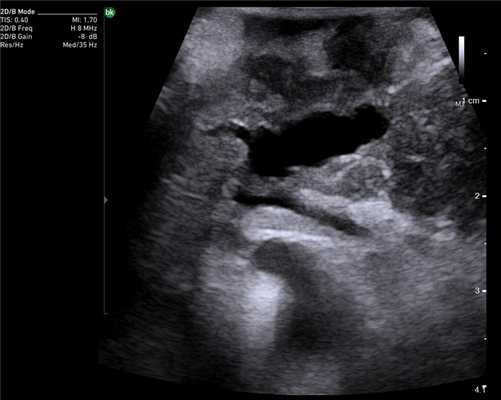

При злокачественных поражениях поджелудочной железы по данным ИОУЗИ проводят окончательную оценку резектабельности и операбельности образований [22]. Взаимоотношение опухоли с окружающими сосудистыми структурами выполняют в продольной и поперечной плоскости сканирования относительно оси сосуда. В первом случае оценивают протяженность контакта и измеряют спектральные характеристики кровотока, во втором - проходимость просвета сосуда и площадь контакта образования с окружностью. По последнему критерию разделяют резектабельные опухоли, когда площадь контакта составляет менее 25% (90º) окружности, условно-резектабельные - опухоль охватывает 25-75% (90º-270º) окружности, нерезектабельные циркулярное вовлечение сосуда более 75% (270º) окружности [23].